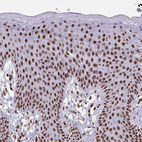

Immunohistochemical staining of human gastrointestinal, kidney, squamous epithelia and testis using Anti-EWSR1 antibody HPA062953 (A) shows similar protein distribution across tissues to independent antibody HPA051771 (B).